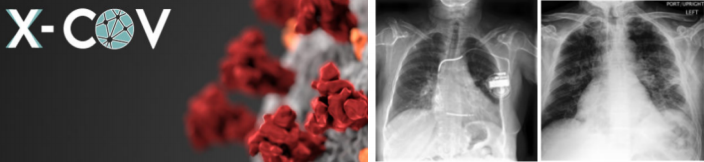

項目名稱:AI技術在肺部醫學診斷的應用(西班牙 X-COV公司)

西班牙馬德里一家初創企業,由醫學院的多名教授和學生聯 合成立,其開發出一款用于協助醫生分析胸腔 X光片的人工智能 工具,這使得醫生對 X光片的分析結論更客觀準確,通過深度學 習,其分析準確率達到 90%以上,假陰性為零。這款工具可通過 線上方式協助醫生,使得因疫情而暴增的 X光片被快速且準確地 分析。同時,該企業在開發新的版本,以融入醫院現有的醫學影 像存檔及傳輸系統。該企業的這款工具在今年的世界級黑客馬拉 松競賽中獲得了眾多醫學專家和公司的關注。